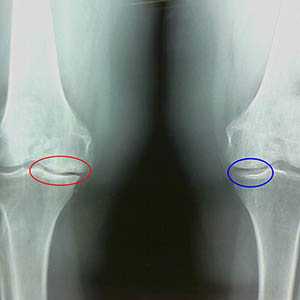

Ранние рентгенологические признаки второй стадии артроза колена:

- заостренные края межмыщелковых бугорков на большеберцовой кости, где крепится крестообразная связка;

- сужение суставной щели на медиальной стороне;

- заостренные края мыщелков костей на медиальных сторонах, реже в латеральной – в зависимости от развития вальгусной или варусной деформации сустава.

Для второй стадии по Ларсену характерно сужение суставной щели более чем на 50%, но проверить это можно только в динамике или сравнении с непораженным суставом.

Рентгенограмма показывает наличие остеофитов, изменение пространства между бедренной и большеберцовой костями, что указывает на потерю хряща в колене. Иногда рентген коленных суставов показывает значительные признаки износа хряща, но пациенты не испытывают значительной боли. Наоборот, артрозы первой стадии могут нарушать функцию колена, поскольку причина боли – гипотоничные мышцы.